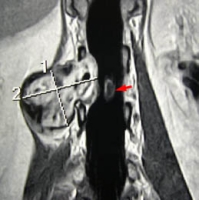

IRM :

- En T1, signal intermédiaire, isointense au muscle

- En T2, hyper signal / graisse

* zones de bas signal au centre lésionnel (target sign)

- après injection de Gadolinium

* rehaussement de signal marqué

- masse hétérogéne, en relation avec pédicule vsculo-nerveux

* vaisseaux nourriciers au niveau des pôles tumoraux

- limites imprécises

- niveaux liquides (zones hémorragiques)

- infiltration de voisinage

- parfois atrophie musculaire

- à l 'étage rachidien, masse en bissac

* intra et extra-rachidienne

* scalloping vertébral

* élargissement foraminal